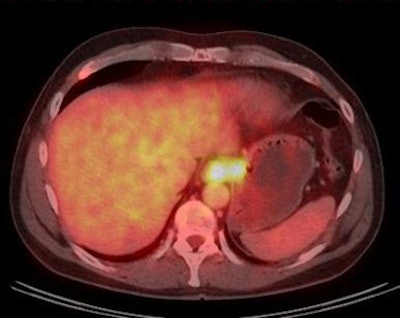

Fully integrated PET/CT, the main workhorse of hybrid imaging, accounts for about 10% of all CT production, with 5,000 units operational worldwide today, and with 95% of use dedicated to initial staging and restaging oncology questions as well as therapy response, 3% used for neuro-oncology, and 2% for cardiology questions.

He suggests part of the answer lies in MR's capacity to yield more information than CT, particularly due to its better soft-tissue contrast and ability to visualize selected aspects of physiological and molecular pathways. Simultaneous PET/MR also allows doctors to follow tracer distributions over time and combine quantitative molecular PET information with information on cellular densities, flow, and perfusion, such as data obtained from advanced MR-based spectroscopy, diffusion, and perfusion studies.